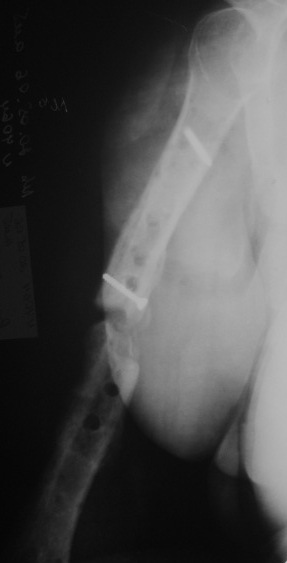

Объективно очевиден лишь тот факт, что не смотря на варианты фиксации перелом несрося за 1.5 года, и по снимку речь вряд ли идет о рефрактуре. Отрицать предположение А.Н.Челнокова о дремлющей инфекции при отсутсвии объективных методов исследования более чем не обосновано. Риск септического воспаления выше чем при первичном остеосинтезе, поэтому выбран более надежный препарат профилактики.

Ну это уже хоть что-то. Вполне может, по этим снимкам показалось, что там периостальные наоения какие-то... остеомиелитно-подозрительные.

На Вашу ситуационную задачу: у нас был аналогичный случай (у пациента Д. за три года было девять ранее перенесенных операци: штифт Богданова с гипсом-пластина-нагноение- аппараты-лечение гнойных ран и остеомиелита - опять dcp пластина-разрушение и миграция пластины....) -

БИОС делали открыто, с декортикацией, частичным торцеванием и костной аутопластикой. Вариант БИОС - компрессирующий). Насчет компрессирующего варианта БИОС потом пожалели - проксимальный блокируемый винт сломался через год, надо было делать стабильный вариант.